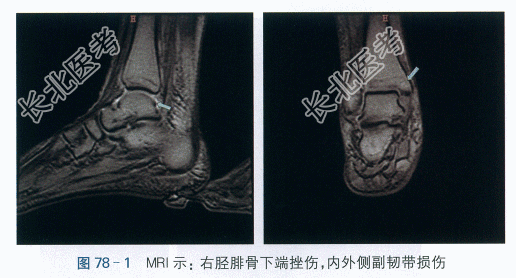

(1)MRI提示:右踝关节肿胀,少量积液,内外侧副韧带损伤,胫骨及腓骨下端斑片异常信号,骨挫伤、水肿,考虑右踝及右足背周围软组织肿胀,如图78-1所示。